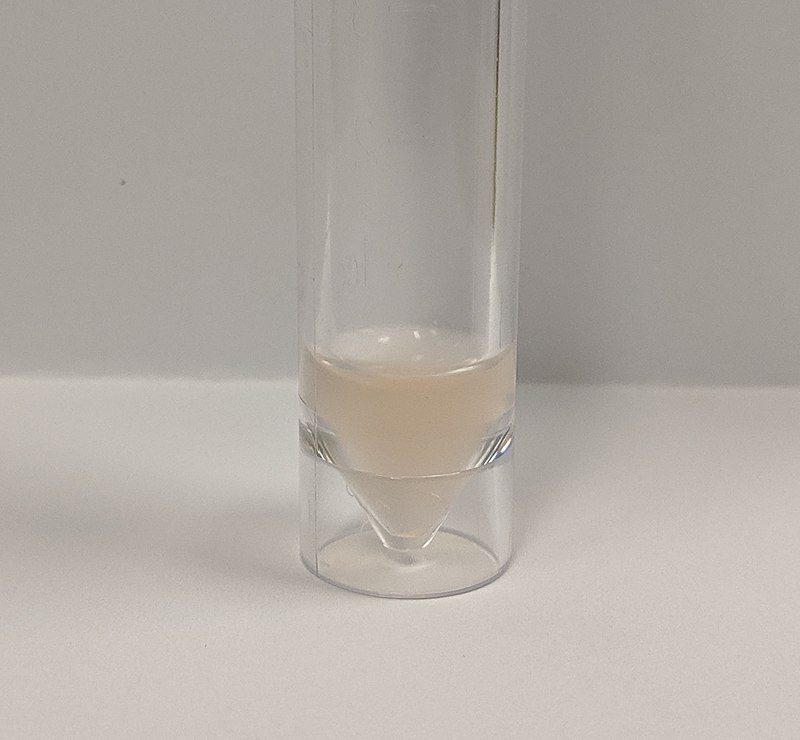

Lumbar puncture is the diagnostic procedure for sampling of cerebrospinal fluid (CSF) to assess meningitis.

Lumbar puncture is performed by inserting a needle between L4 and L5 (level of the iliac crest).

Note that the spinal cord ends at L2, but subarachnoid space and cauda equina continue.

Cerebrospinal fluid (CSF) findings in meningitis depend on the cause.